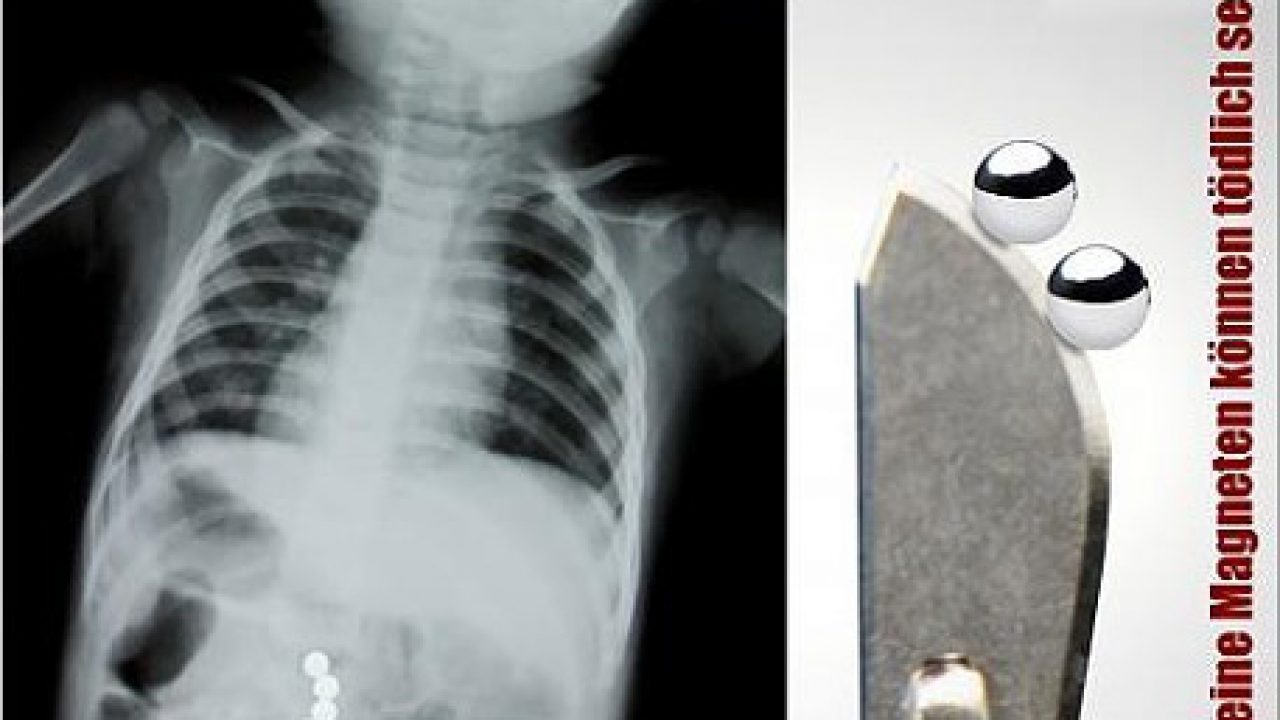

Kleinkinder Oft Lebensbedrohlich Erste Hilfe Bei Verschluckten Kleinteilen Oder Magneten Cleankids Magazin

Erste Hilfe Was Tun Wenn Das Kind Magneten Verschluckt Welt